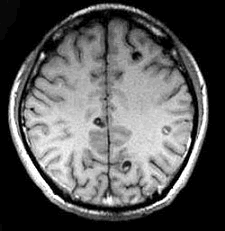

男,29岁。头痛不适半个月。MRI扫描如图示。据此可作出以下最可能的诊断是()

A.脑转移瘤

B.脑囊虫病

C.脑弓形虫病

D.脑脓肿

E.未见异常

[单选题]男,29岁,头痛不适半个月,MRI扫描如图,最可能的诊断是()A.脑转移瘤B.脑囊虫病C.脑弓形虫病D.脑脓肿E.未见异常

[单选题]男,29岁。头痛不适半个月。MRI扫描如图示。据此可作出以下最可能的诊断是()A . 脑转移瘤B . 脑囊虫病C . 脑弓形虫病D . 脑脓肿E . 未见异常

[单选题]男,29岁。头痛不适半个月。MRI扫描如图示。据此可作出以下最可能的诊断是()A .脑转移瘤B .脑囊虫病C .脑弓形虫病D .脑脓肿E .未见异常

男,29岁,头痛不适半个月,MRI扫描如图,最可能的诊断是()

[单选题]男,29岁,头痛不适半个月,MRI扫描如图,最可能的诊断是()A . 脑转移瘤B . 脑囊虫病C . 脑弓形虫病D . 脑脓肿E . 未见异常

男,29岁,头痛不适半个月,MRI扫描如图,最可能的诊断是()

[单选题]男,29岁,头痛不适半个月,MRI扫描如图,最可能的诊断是()A .脑转移瘤B .脑囊虫病C .脑弓形虫病D .脑脓肿E .未见异常